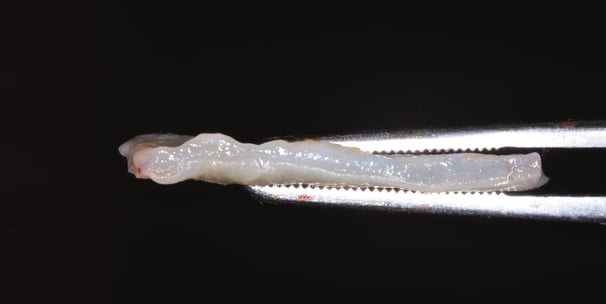

Rasul Guliyev, Bakü, Azerbaycan doğumludur. 2018 yılında Ege Üniversitesi Diş Hekimliği Fakültesi’nden mezun olmuş, ardından 2018-2022 yılları arasında Ondokuz Mayıs Üniversitesi Diş Hekimliği Fakültesi Periodontoloji anabilim dalında uzmanlık eğitimini tamamlamıştır. Uzmanlık tezini “Dişeti Fenotipinin Klasifikasyonunda Kullanılan Geleneksel ve Güncel Yöntemlerin Karşılaştırılması” üzerine yapmıştır.

Periodontal hastalıkların teşhis ve tedavisi, implantoloji ve estetik diş hekimliği alanlarında ileri seviye uygulamalarda uzmanlaşmış olup, bu konularda akademik ve klinik çalışmalarını sürdürmektedir. Güncel teknolojileri ve yenilikçi tedavi yaklaşımlarını takip ederek hastalarına en yüksek standartlarda sağlık hizmeti sunmayı amaçlamaktadır.